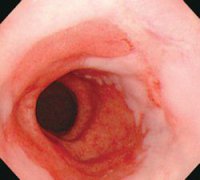

• Barrett食管綜述-巴雷特氏食管

食管下段的鱗狀上皮被柱狀上皮覆蓋,因為英國人Barrett首先報道,因此稱 Barrett食管 ,中文翻...

• Barrett食管癥狀及檢查

常見癥狀 便血 惡心與嘔吐 燒心 吞咽困難 胸骨后疼痛 BE本身并無癥狀,其癥狀主要是由于胃食...